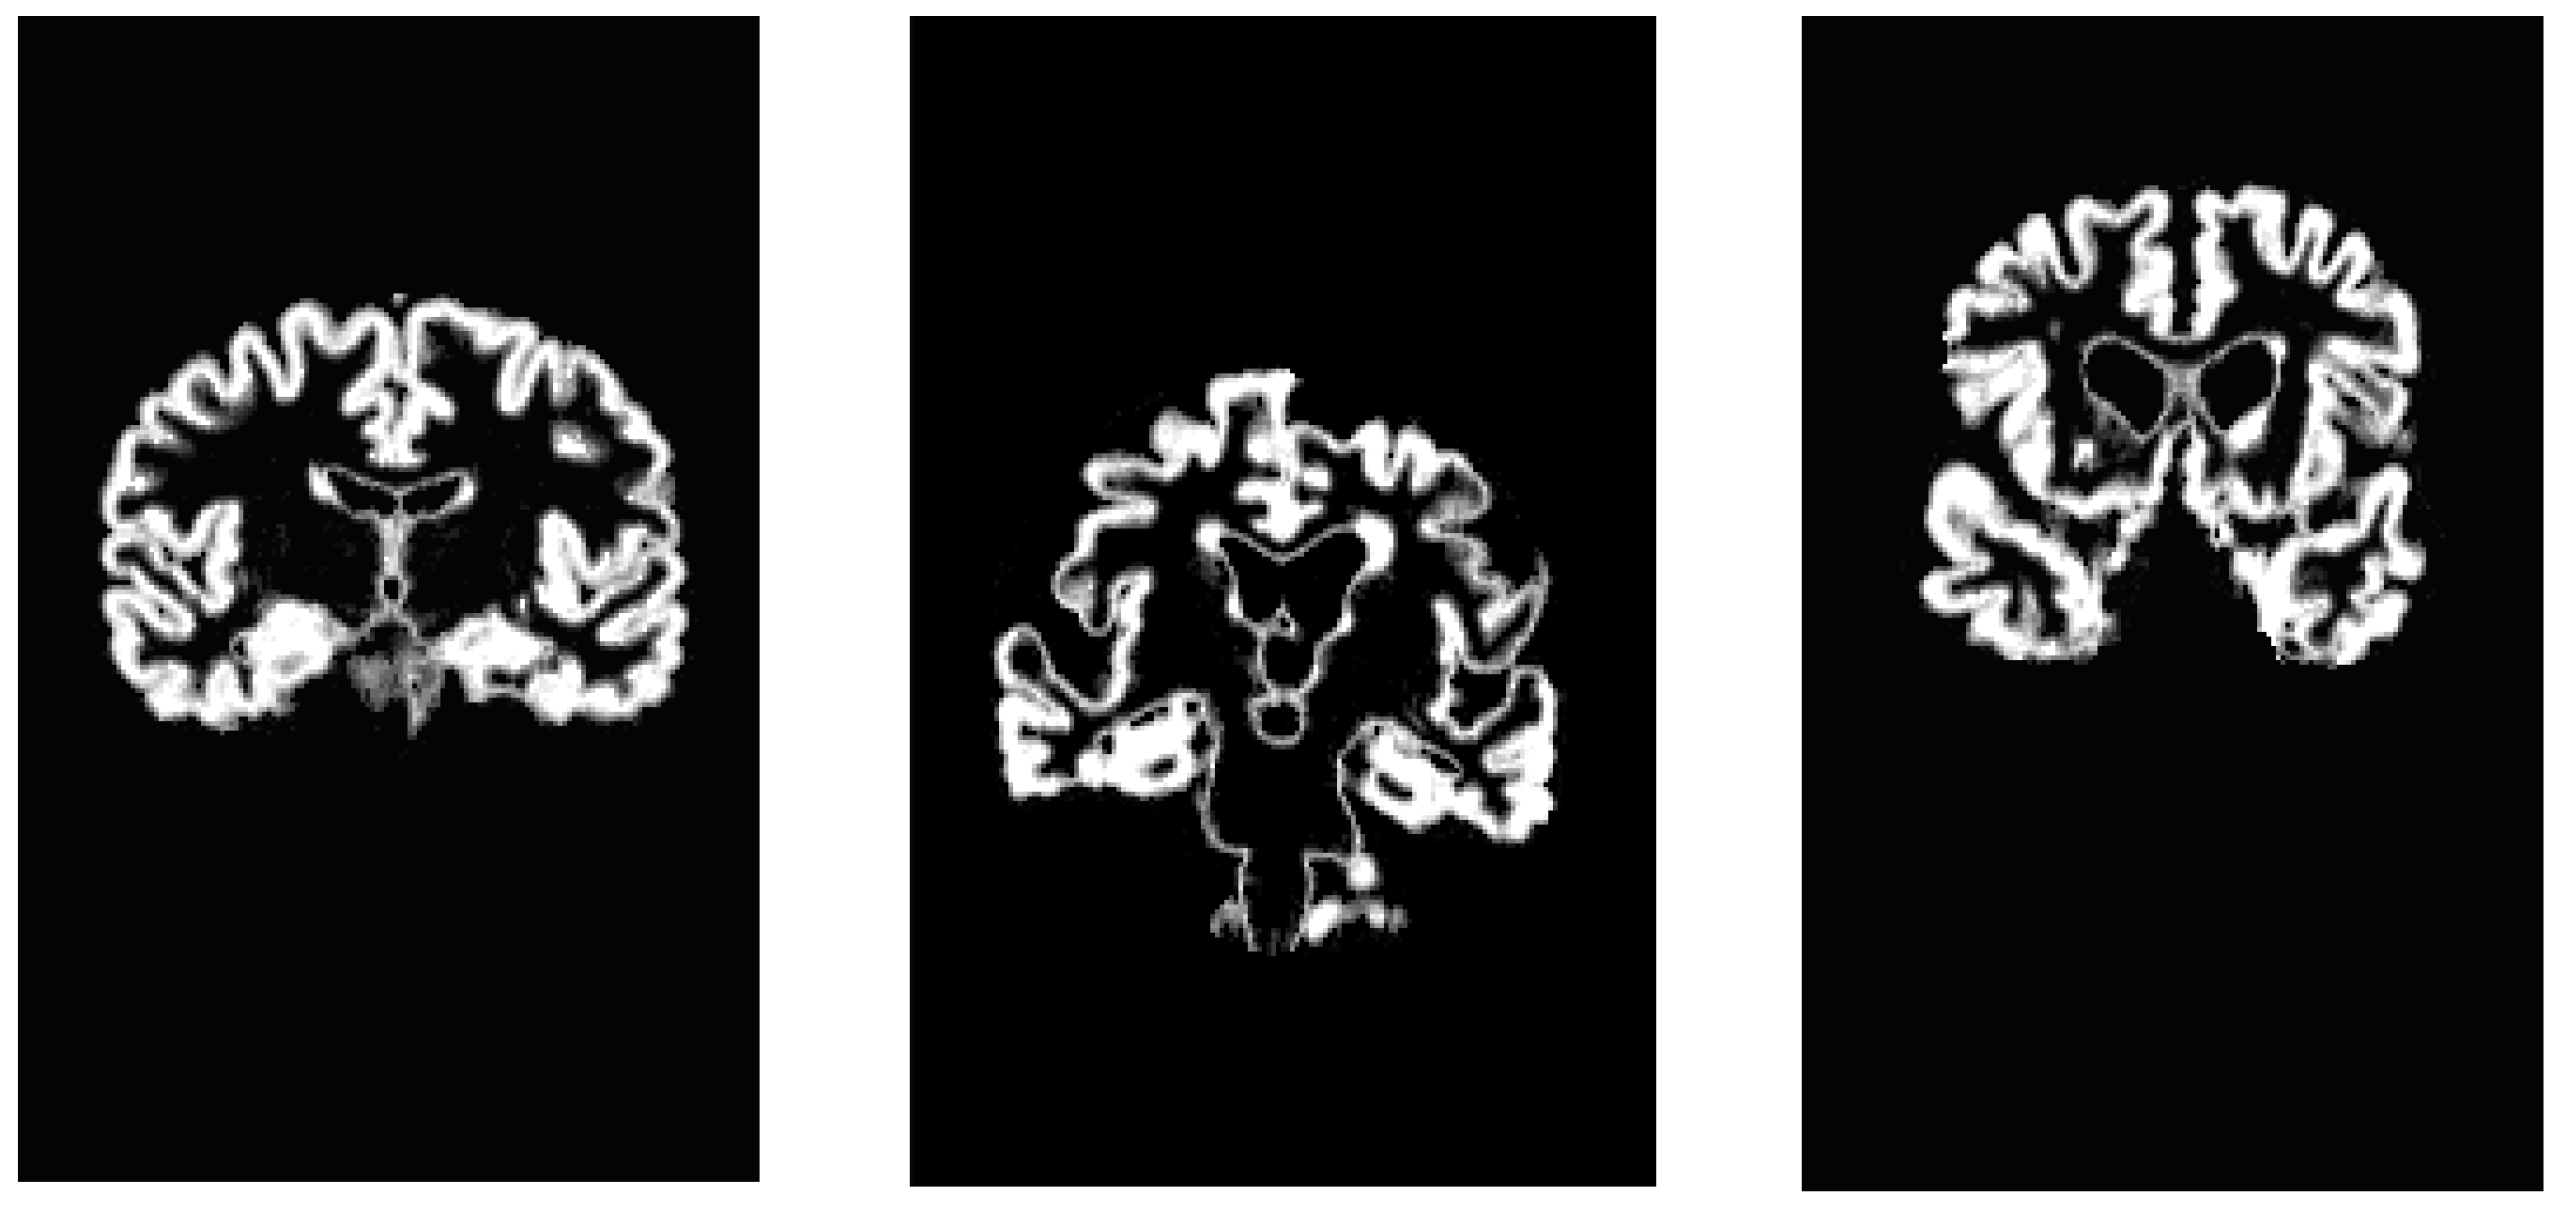

For what concerns DTI images, this approach is addressed to demarcate the areas with higher diffusivity of water molecules. We could note the high level of noise present in them; in order to perform a noise reduction, images are initially pre-processed applying a median digital filter (Figure 16). As previously mentioned, the most significant information of a grayscale FA map are taken from zones with high intensity levels corresponding to preferential directions of water diffusion, presumably along axonal bundles. Thus after analyzing the intensity distribution of image pixels (Figure 17 and Figure 18), we have obtained an image segmentation by using thresholds ranging from 180 to 210. Subsequently, edge extraction has been performed through an automatic selection of an initial contour from the level curves of the divergence map (Figure 18, Figure 19 and Figure 20).

Figure 16. (a) DTI image for a non-pathological subject; (b) Filtered FA map.

Algorithms 05 00636 g016